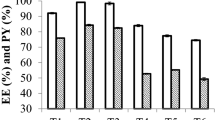

The formulations were stable based on drug EE, and cumulative % drug release (CDR %) after their storage for 3 months (90 days) at 40 ± 2 °C, 75 ± 5% RH. Also, the spreadability, viscosity, and pH of LoR-NS gel were stable in the same experimental conditions. The data obtained with LoR-NS suspension corroborate previously published data38. There was no significant difference (p > 0.05) in stability after 2 months, and the slight changes observed in its pH, %CDR, viscosity and % EE but not significantly difference after 90 days as given in Table 5 and Fig. 8. Mainly pH reduction observation was due to hydrolysis (LoR might undergo hydrolysis usually at high temperatures) or oxidation with chemical reactions and degradation of buffers in the formulations39. The stability study conclude that the optimized formulation should remain stable when topically applied in humans.